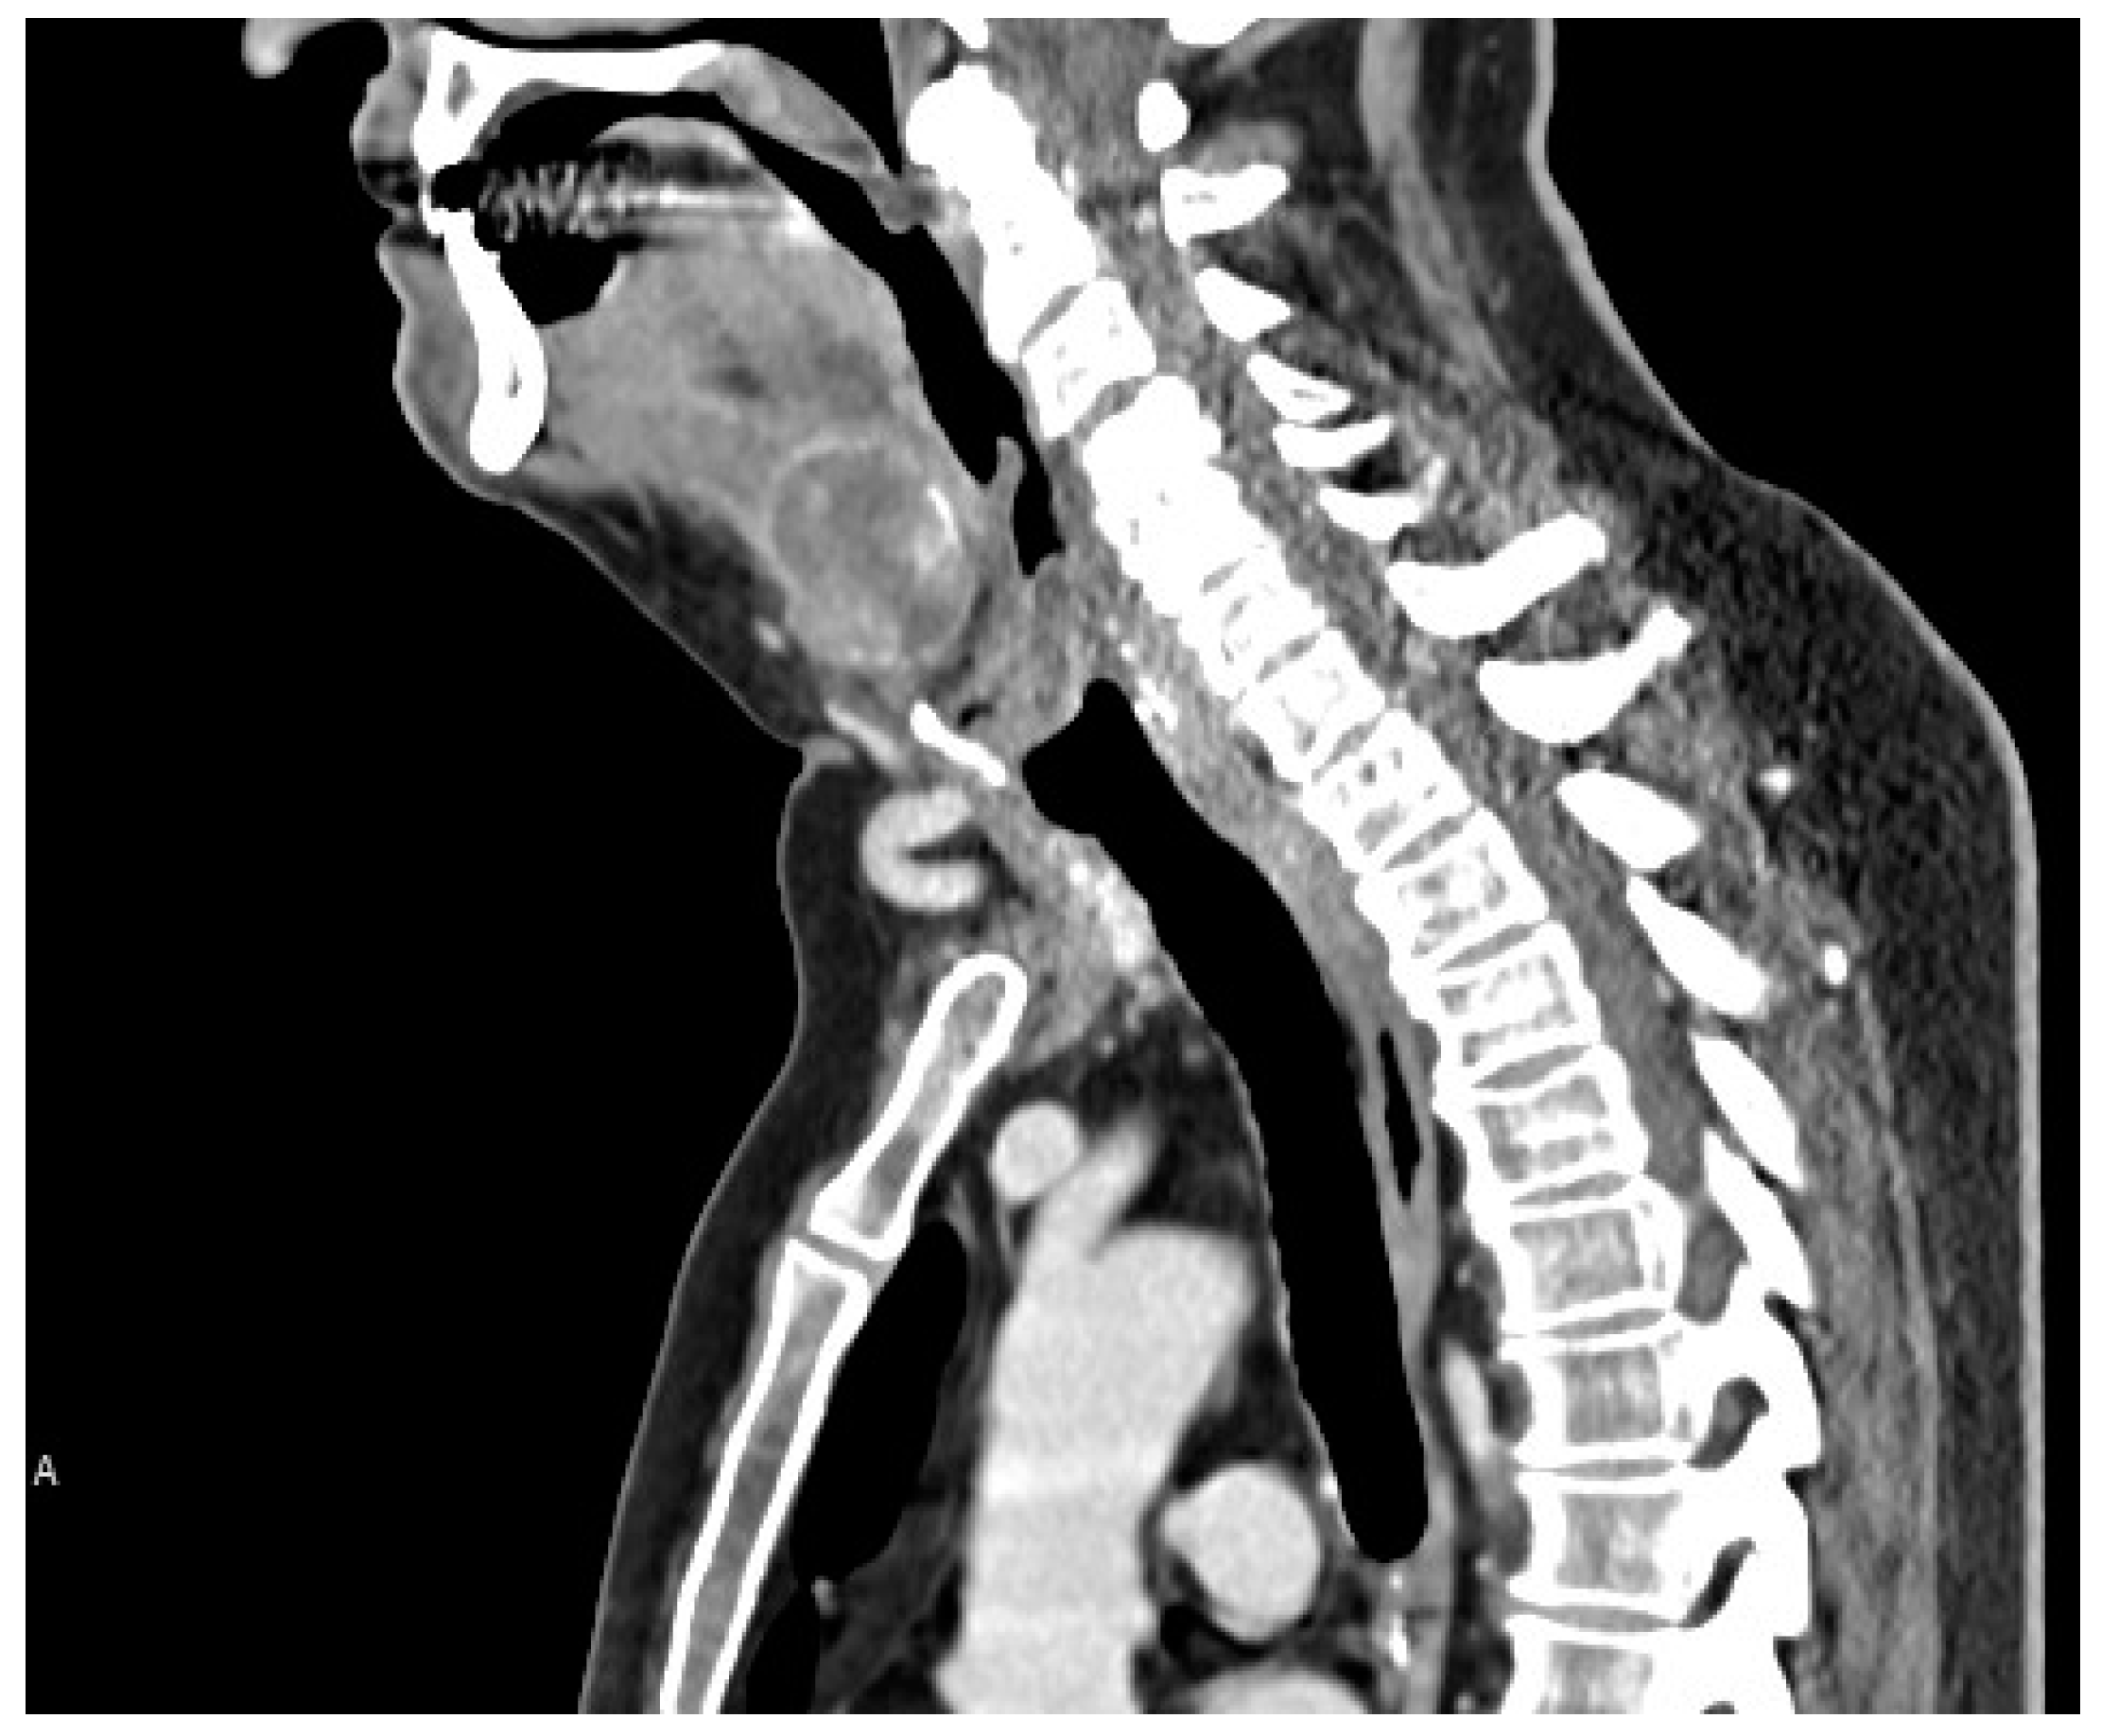

A rounded osteolytic mass of 4.5 × 3.6 cm in size in the central part of the hyoid bone was evident from a contrast-enhanced computed tomography (CT).

CT demonstrated massive osteolysis and cortical destruction with the enlargement of the body of the hyoid bone. The osteolytic mass of the hyoid bone showed a slight soft tissue extension toward the pre-epiglottic region. An evident extension towards pre-hyoid muscles was also noted. The lumen of the airways was not affected, and no pathological changes were evident in the surrounding structures of the neck (Figure 1, Figure 2 and Figure 3).

Figure 2. Contrast-enhanced computed tomography (CT) showed a rounded osteolytic mass of 4.5 × 3.6 cm in size in the central part of the hyoid bone: sagittal view.